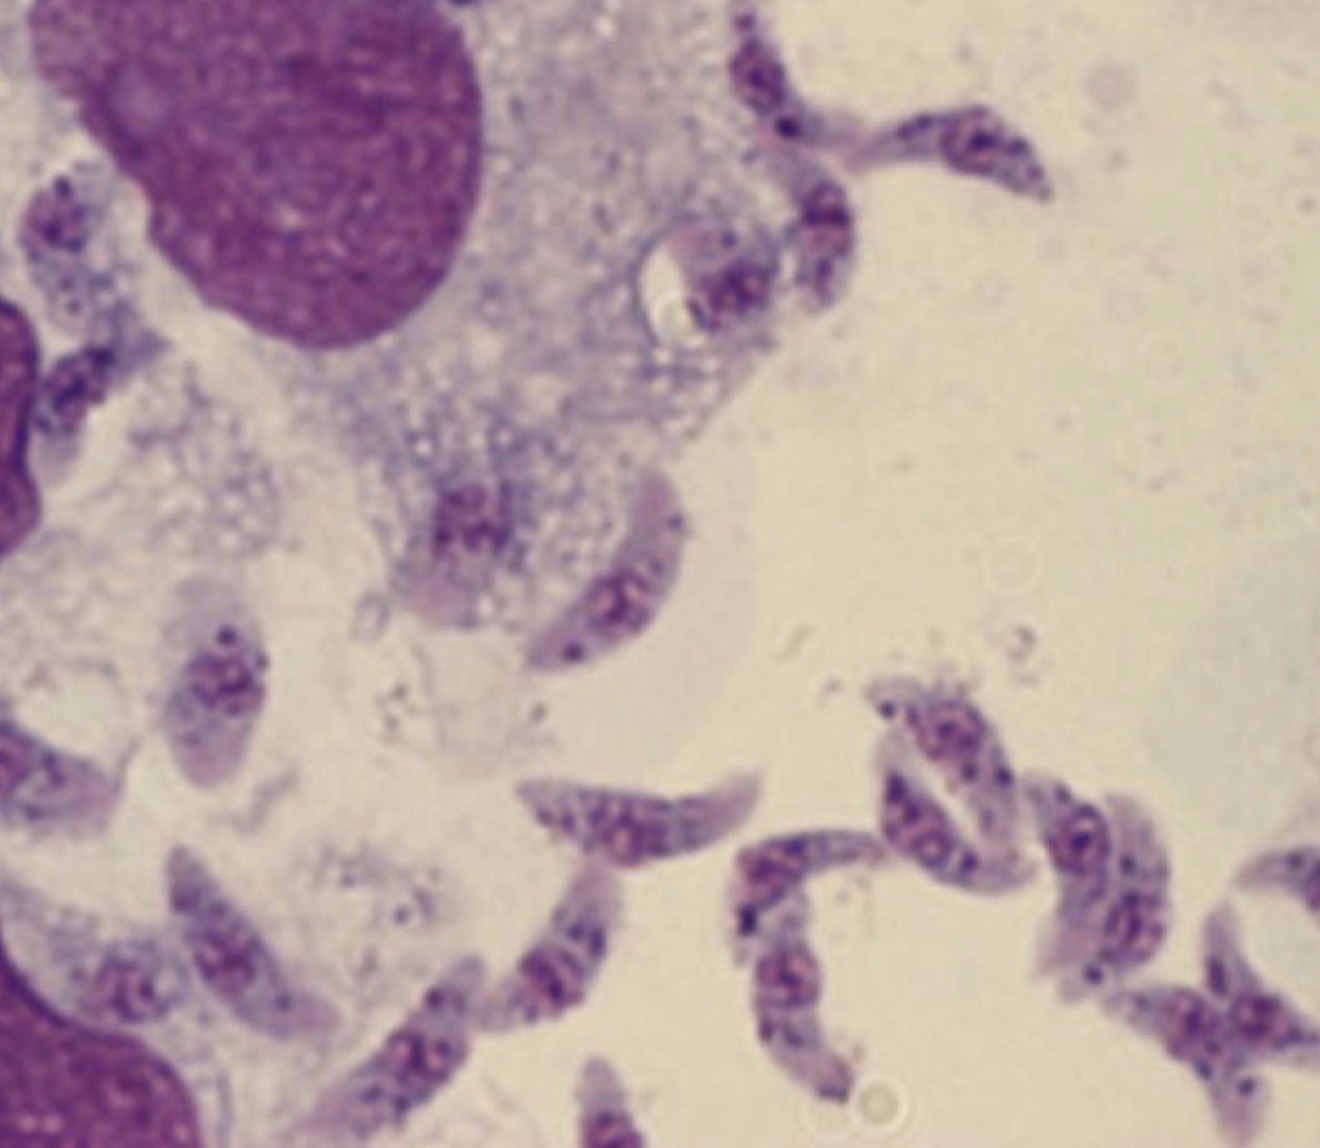

Tripomastigote de Trypanosoma cruzi

Epimastigote de Trypanosoma cruzi

Tripomastigote de Trypanosoma brucei

Tripomastigote de Trypanosoma rangeli